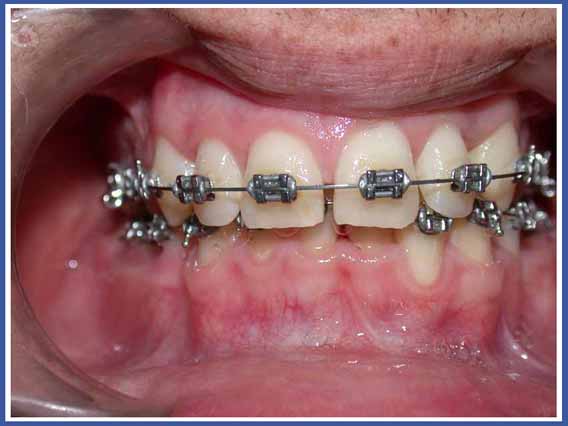

Это на сегодняшний день наиболее распространенное приспособление для выпрямления зубов. Брекеты приклеиваются к зубам, и проволочка, проходящая между ними, позволяет смещать зубы во всех трех измерениях при полном контроле над смещением, в отличие от пластинок, которые могут изменять только угол расположения зубов относительно челюсти. Брекеты могут быть как металлическими, так и прозрачными.

Брекеты, приклеиваемые к зубам, обладают многими преимуществами, но у них есть также и недостатки. Основной недостаток – это накопление остатков пищи и появление на нем микробов. Чтобы избежать опасности появления кариеса (дырок), нужно тщательнейшим образом чистить зубы в период лечения, и, насколько это возможно, избегать употребления пищи, ускоряющей развитие кариеса (пищи, богатой сахаром).